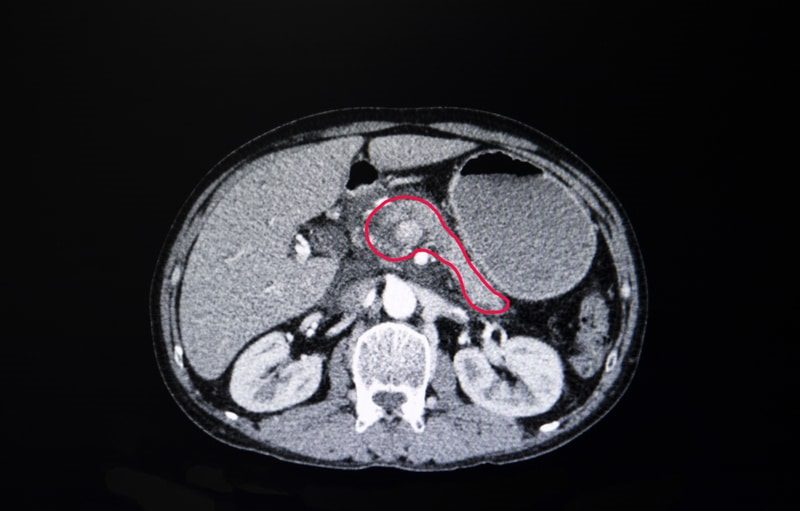

Vascular invasion assessment is critical for surgical planning in pancreatic ductal adenocarcinoma (PDAC). Current CT-based assessments often rely on radiologists’ subjective 2D interpretations, which may not capture the continuous, three-dimensional tumor–vessel interactions and multiple…